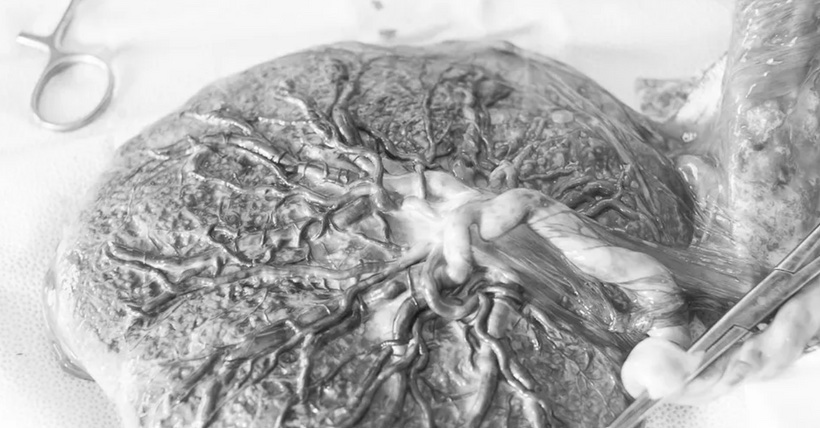

Now look at the human placenta below.

Doesn’t it look similar? Nature’s decentralized networks always rhyme because of their fractal design.